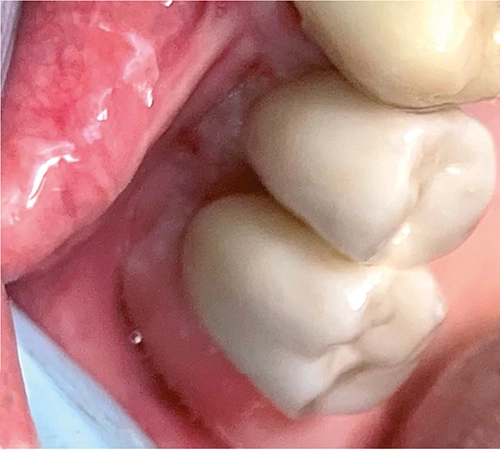

Der Praktiker schätzt vor allem im distalen Bereich das einfache Einsetzen der Rekonstruktion ohne Manipulation mit einem Schraubendreher. Der Patient wird aufgefordert, fest auf einen Holzspatel zu beißen, um die Reibhaftung zu aktivieren (Abb 8a-c).